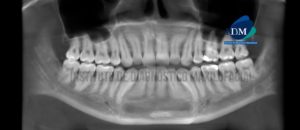

Paciente masculino de 42 años de edad es referido al Instituto de Diagnóstico Maxilofacial (IDM) para evaluación general. En la reconstrucción panorámica (Figura 1)se observa